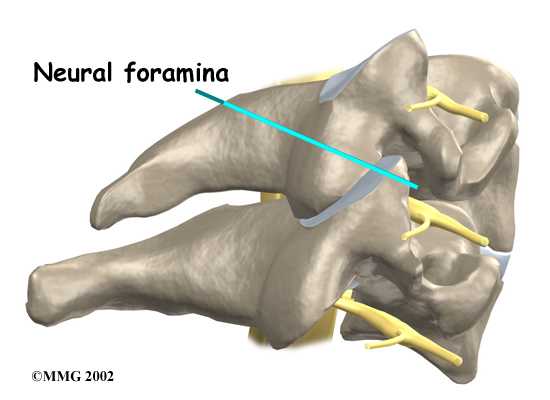

Two spinal nerves exit the sides of each spinal segment, one on the left and one on the right. As the nerves leave the spinal cord, they pass through a small bony tunnel on each side of the vertebra, called a neural foramen. (The term used to describe more than one opening is neural foramina.)

Neural Foramen

As the degeneration continues, bone spurs develop around the facet joints and around the disc. No one knows exactly why these bone spurs develop. Most doctors think that bone spurs are the body's attempt to stop the extra motion between the spinal segment. These bone spurs can cause problems by pressing on the nerves of the spine where they pass through the neural foramina. This pressure around the irritated nerve roots can cause pain, numbness, and weakness in the neck, arms, and hands.

- Degeneration: As the spine ages, several changes occur in the bones and soft tissues. The disc loses its water content and begins to collapse, causing the space between the vertebrae to narrow. The added pressure may irritate and inflame the facet joints, causing them to become enlarged. When this happens, the enlarged joints can press against the nerves going to the arm as they squeeze through the neural foramina. Degeneration can also cause bone spurs to develop. Bone spurs may put pressure on nerves and produce symptoms of cervical radiculopathy.

X-rays show problems with bones, such as infection, bone tumors, or fractures. X-rays of the spine also can give your doctor information about how much degeneration has occurred in the spine, by showing the amount of space in the neural foramina and between the discs. X-rays are usually the first test ordered before any of the more specialized tests. Special X-rays called flexion and extension X-rays may help to determine if there is instability between vertebrae. These X-rays are taken from the side as you lean as far forward and then as far backward as you can. Comparing the two X-rays allows the doctor to see how much motion occurs between each spinal segment.

A foraminotomy is done to open up the neural foramen and relieve pressure on a spinal nerve root. A foraminotomy may be done because of bone spurs or inflammation.